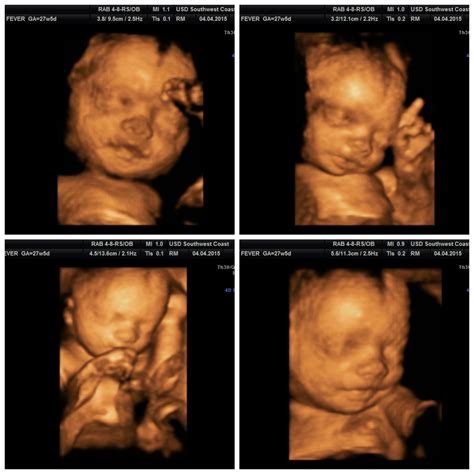

28 Weeks Pregnant Sonogram

Pregnancy is a journey filled with excitement, anticipation, and a multitude of milestones. One of the most significant milestones is the 28 weeks pregnant sonogram. This ultrasound scan provides crucial insights into the baby's development and the mother's health. Understanding what to expect during this scan can help alleviate any anxieties and prepare you for the experience.

The 28 weeks pregnant sonogram is typically part of the routine prenatal care schedule. This ultrasound is often referred to as the anatomy scan or the mid-pregnancy ultrasound. It is usually performed between 26 and 28 weeks of pregnancy. The primary goal of this scan is to assess the baby's anatomy and development, ensuring that everything is progressing as it should.

• Images and Measurements: The technician will take detailed images and measurements of your baby's organs, limbs, and overall development. This includes checking the baby's heart, brain, kidneys, and other vital organs.

• Baby's Growth: The baby's size, including the head circumference, abdominal circumference, and femur length, will be measured to ensure the baby is growing at a healthy rate.

• Organ Development: The technician will check the development of the baby's organs, including the heart, brain, kidneys, and lungs. Any abnormalities will be noted for further evaluation.

• Baby's Movement: The baby's movements, such as sucking their thumb, kicking, or rolling, may be observed. This is a reassuring sign of the baby's health and development.